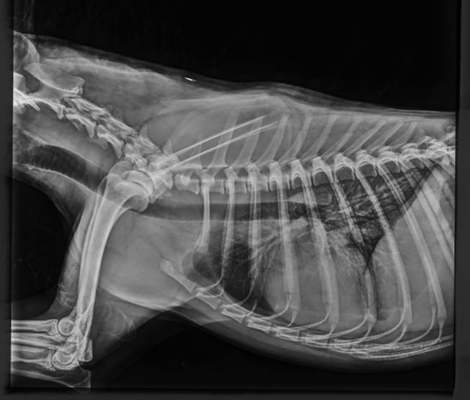

Hip & Elbow x-rays

Perhaps one of the most well known health testing in dogs, hip and elbow x-rays taken to check for signs of dysplasia. Once taken by a qualified vet the x-rays are then sent to a scoring board dependent on country of residence or personal choice of the breeder. To the right, is a comparison of the results across the most common available testing organisations.

The organisation which we primarily use for our program is BVA.

Elbows: Elbows are graded individually with a score from 0-3 on each side. The ideal being a score of 0. To have an elbow scored there must be at least two x-rays; flexed lateral and neutral view. Elbow dysplasia is uncommon in both Komondor and Mudi.

Hips: Under the BVA scheme, the marking of hips is broken down into 9 sections, the maximum marks in any one section is 6, and the maximum overall is 106. The aim is to obtain the combined lowest number possible, the best result possible being a 0. Please view the example images of our dogs results attached above to see the 9 possible sections.